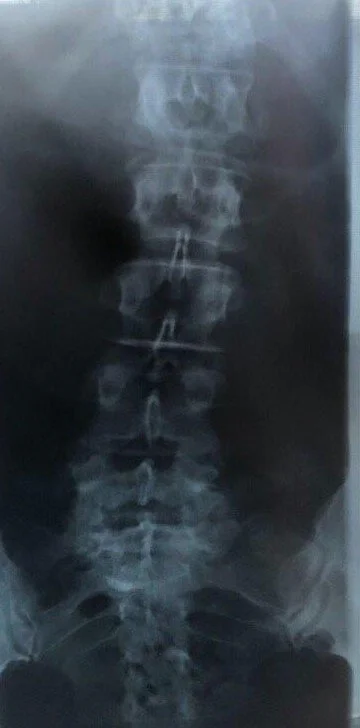

Initial checkup was performed by a medical doctor dated 09.December.2019. Based on Xray findings , medical diagnostic paperwork was issued to the patient. (left original, right translation)

X-ray thoracic spine / lumbar spine in 2 planes from 09.12.2019.

Intact framework structures of the vertebral bodies of the thoracic spine without wedge-shaped deformations, with distinct spondylotic marginal spurs, intact pedicles. A significant scoliotic malposition cannot be documented.

Smooth contours of the lumbar vertebrae without wedge-shaped deformations, with distinct sclerosis of the facet joints in the lumbo-sacral transition area, without continuity interruptions. The sacroiliac joints present as smoothly defined.

• Distinct spondylosis deformans of the thoracic spine without wedge-shaped deformations.

• No significant scoliotic malposition of thoracic and lumbar spine.

• Caudally emphasized spondylarthrosis in the lumbar spine region.